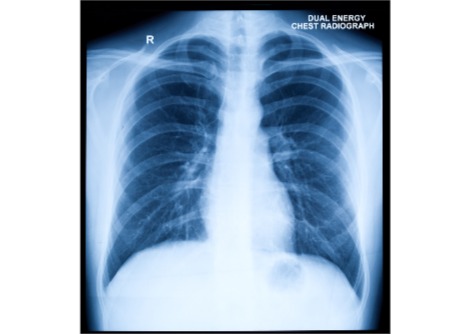

لماذا تتزايد معدّلات الإصابة بمرض السرطان؟

Cancer Research UK أعلنت عن إحصائيّة مثيرة للعجب والقلق في آنٍ واحد، وهي أنّ شخصًا واحدًا من بين كلّ اثنين في المملكة المتحدة سيُصاب بمرض السّرطان في مرحلة ما من حياته. هذه الإحصائيّة الجديدة تُظهرُ فرقًا كبيرًا إذا ما قورِنَتْ بالتّوقُّع السّابق الّذي بيّن إصابة شخص واحد من بين ثلاثة.

أوّلًا، معدّل المتعافين من مرض السّرطان تضاعف على مدى السّنوات الأربعين الأخيرة، ونصف المرضى الآن ينجحون بالتّغلّب على المرض لأكثر من 10 أعوام. الإحصائيّة الجديدة نتجت عن طريقة حساب تختلف عن تلك الّتي أظهرت مرض شخص واحد من بين ثلاثة، وهي أكثر دقّة أيضا.

إذن لماذا يتزايد عدد المصابين بدلًا من أن يقلّ؟

يربط الباحثون الأمرَ باعتماد أسلوب حياة صحّيّ مّما يزيد من طول عمر الفرد. لهذا السبب يتزايد خطر الإصابة بمرض السّرطان، فقد قدّر الباحثون الثلث المتزايد على أنه متعلّقٌ بطول حياة الفرد، وهذا يعني أنّ الكثيرين يتّبعون أسلوب حياة يمتاز بالصّحّة.